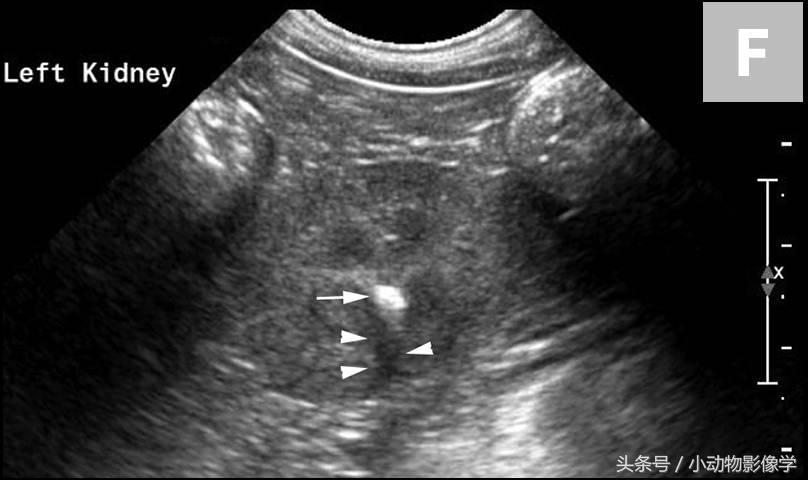

图3E、这是另一只狗左肾X光片的特写,肾盂区域内有小型肾结石(箭头)。

图3F、图3E中左肾的超声图像。与图3B和3D相比,由于该犬的结石(箭头)体积较小,所以远端声影伪像很小(三角箭头)。